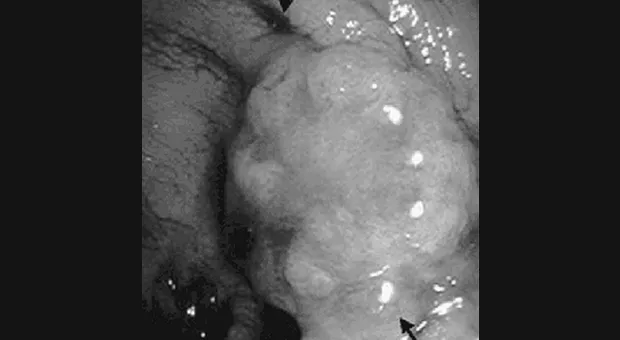

Поражения желудка

Ono с коллегами [30] выполнил EMR у 445 пациентов с поверхностными поражениями желудка. При патологическом процессе ограниченном слизистой оболочкой полноценная резекция (т.е. когда края препараты были свободны от патологических клеток) была выполнена в 69 % (278/405), в то время как резекция была неполной в 31 % случаев (127/405). Уровень рецидива составил 2 % и 17 % соответственно. Не наблюдалось смерти связанной с раком желудка при наблюдении средней длительности в 38 месяцев. Во всех случаях рецидива проводились радикальные вмешательства.

Yoshikane с сотрудниками [31] исследовал возможность выполнения эндоскопической аспирационной резекции слизистой кускованием для поверхностных внутрислизистых опухолей желудка большего размера. У всех пяти пациентов был рак желудка размером 4 или более см (средний размер 4,8 см). Была выполнена эндоскопическая аспирационная резекция слизистой кускованием с помощью панэндоскопа с насадкой. За время наблюдения в течение 16,4 ± 1,1 месяца у одного пациента была выявлена остаточная опухоль (или ее рецидив), у 4 опухоли не наблюдалось.